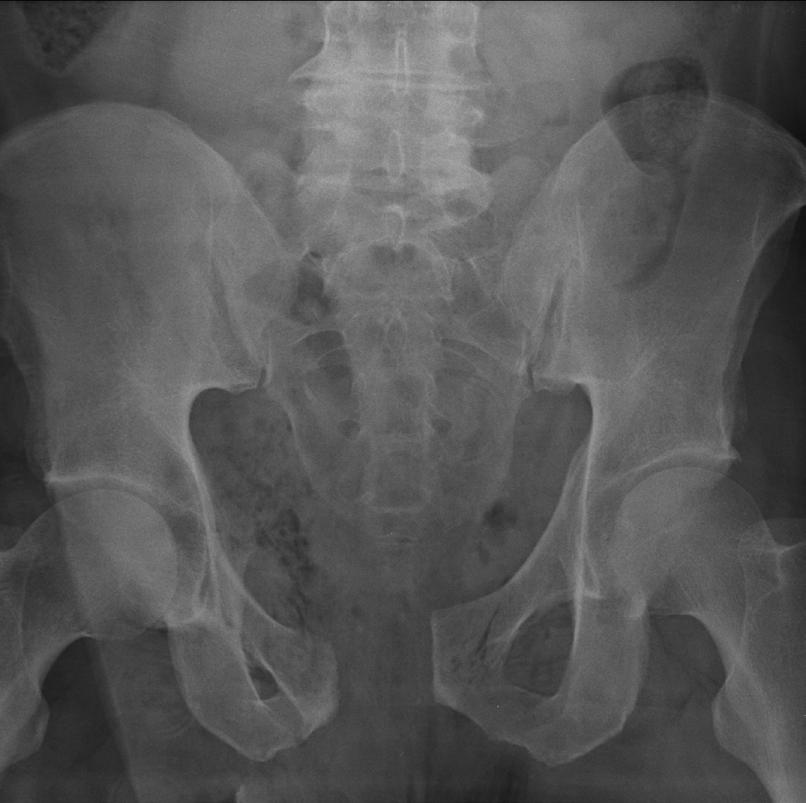

Mr. Smith is found to have a low blood pressure, presumably due to ongoing major bleeding. Additional whole blood and tranexamic acid are immediately administered and the trauma massive transfusion protocol is activated. Immediately available bedside x-ray and ultrasound imaging reveal no major bleeding in the chest or abdomen but concern for a major pelvic fracture with ongoing bleeding. The trauma and orthopedic teams place a pelvic binder device to rapidly slow major bleeding, and a catheter with a balloon tip is placed into the abdominal aorta via the right groin in order to stop major blood flow into the pelvis and slow bleeding. Meanwhile, a timer on the wall of the trauma bay keeps track of resuscitation time with a goal disposition of 15 minutes to the next phase of care.

With improved vital signs, Mr. Smith is taken to one of two state-of-the-art CT scanners immediately adjacent to the trauma bay within 15 minutes of arrival. The team closely monitors the patient from the CT control room during his scan while watching his vital signs via the portable cardiac monitor. The additional imaging confirms multiple pelvic fractures with active bleeding. The on-call interventional radiology team is consulted and within 60 minutes performs a minimally invasive intervention to stop bleeding from the major arteries in the pelvis. The previously placed aortic catheter is removed.